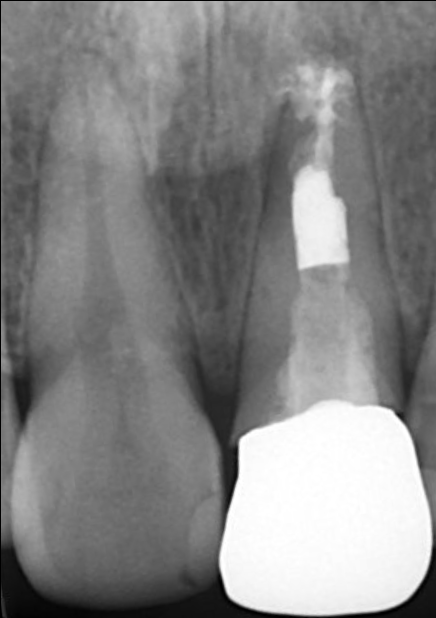

初診時の口腔内写真とデンタルX線写真

インプラントSET後の口腔内写真とデンタルX線写真